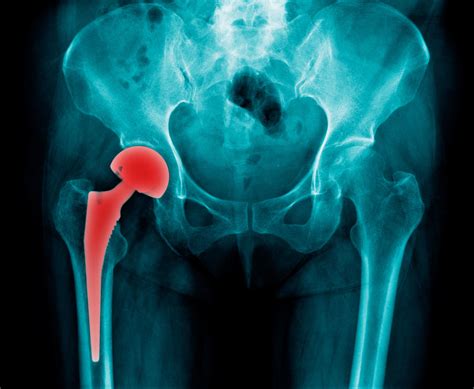

The cadera, or hip, is a complex joint that connects the pelvis to the femur (thighbone). It is a ball-and-socket joint, where the femoral head (ball) fits into the acetabulum (socket) of the pelvis. This structure allows for a wide range of motion, including flexion, extension, abduction, adduction, and rotation.

• Surgery: In severe cases, surgery may be necessary to repair or replace the cadera. Common procedures include hip arthroscopy, hip replacement, and hip resurfacing.